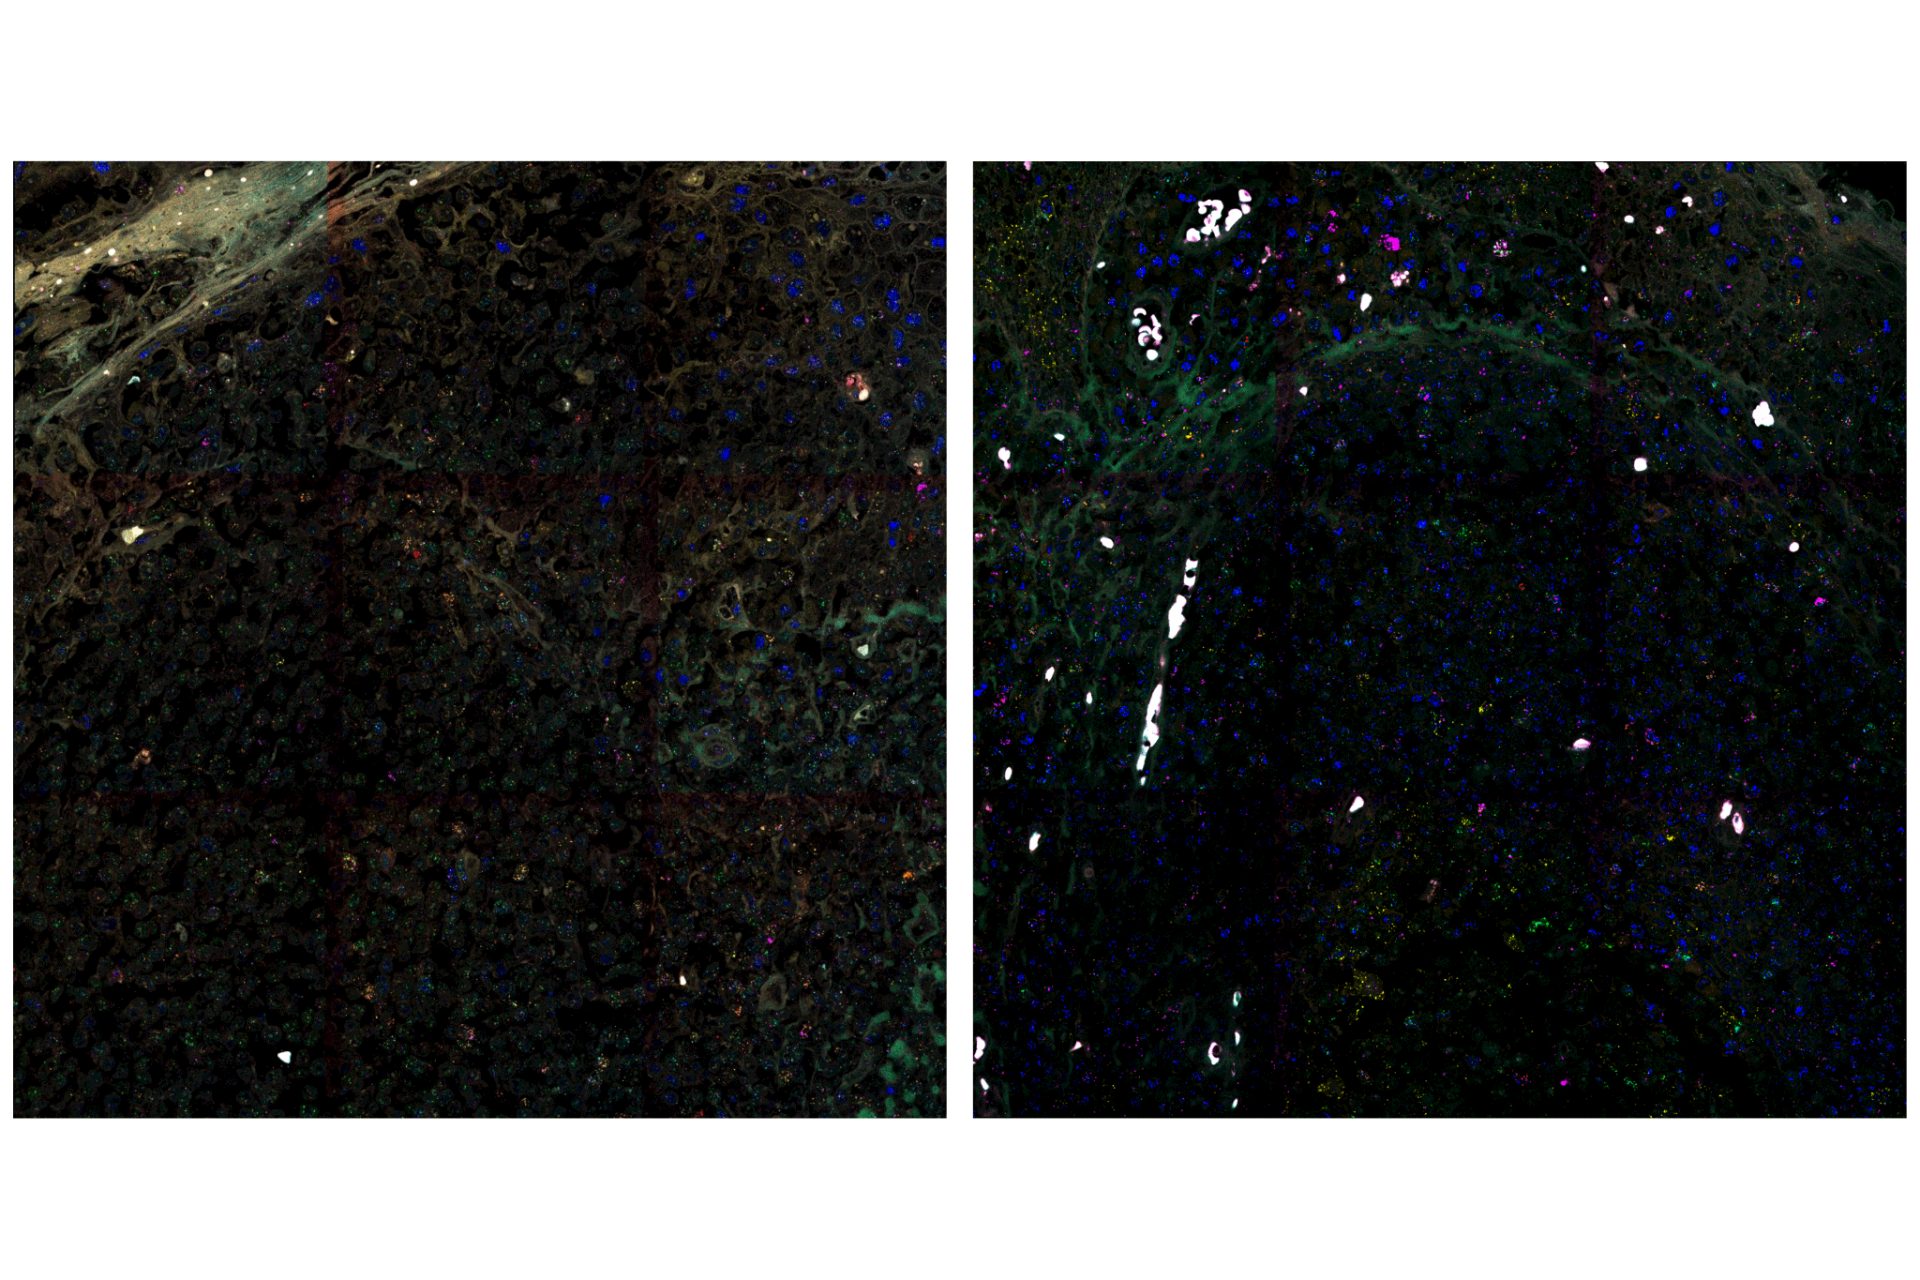

Human tonsil tissue stained with multiple cancer markers

The human tonsil, a strategically positioned lymphoid organ, is designed for robust immune surveillance, featuring distinct functional regions, where a diverse array of immune cell facilitates the intricate dynamics of pathogen response and immune regulation. Understanding the distribution of the expression of different genes in the tissue, allows for the visualization of the diverse range of cell types, including epithelial cells, T cells, B cells, macrophages, and proliferating cells, as well as proteins involved in immune regulation and tumor microenvironment interactions. In this case study a comprehensive labeling panel (Figure 1B) allowed for a detailed exploration of the complex cellular architecture and functional dynamics of the tonsil, providing a foundation for understanding the spatial context of gene expression.

Simultaneous visualization of these 9 markers allows for a comprehensive understanding of cellular interactions and functional states within the tonsil's complex architecture. By meticulously mapping the spatial relationships between diverse cell types and key signaling molecules, we can uncover nuanced insights into tissue organization and biological processes that would be completely obscured when examining markers in isolation. This multi-marker approach enables the creation of a detailed spatial map, revealing how different cell populations are organized and how their interactions contribute to the overall tissue function. This level of detail is essential for understanding complex biological processes like immune responses and disease progression.

• Figure 2A: Marker Overlay

• Figure 2B: Pure spectra for the 9 markers. Different markers are expressed in different regions of the tissue.